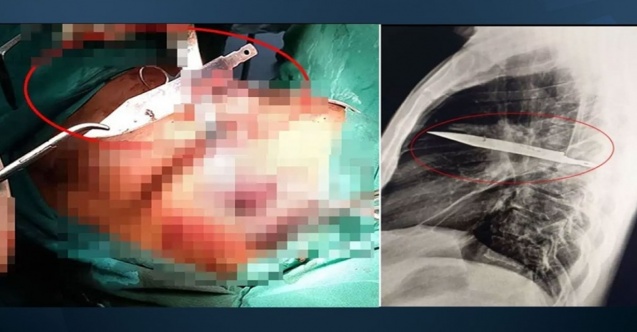

Tanzanya’da 44 yaşındaki bir adam, sağ memesinin altından iltihap akması şikâyetiyle hastaneye başvurdu.

İlk muayenede ağrı, nefes darlığı, öksürük ya da ateş belirtisi görülmedi.

Ancak yapılan röntgen sonucu herkesi şaşkına çevirdi. Adamın göğsünde tam 8 yıldır saplı duran bir bıçak vardı.

Hasta, yıllar önce yaşadığı şiddetli bir kavga sırasında yüzünden, sırtından, göğsünden ve karnından yaralandığını, o dönemde tedavi gördüğünü anlattı.

O günden bu yana ciddi bir sağlık sorunu yaşamayan adam, yalnızca son günlerde fark ettiği iltihap nedeniyle doktora gitmişti.

Bıçağın sağ kürek kemiğinden girerek hayati organlara zarar vermeden göğüste kaldığı belirlendi.

Yapılan ameliyatla bıçak çıkarıldı ve ölü dokular temizlendi.

Hasta, yoğun bakımda bir gün, normal serviste ise 10 gün kaldı. Doktorlar, yapılan kontrollerde hastanın tamamen iyileştiğini duyurdu.